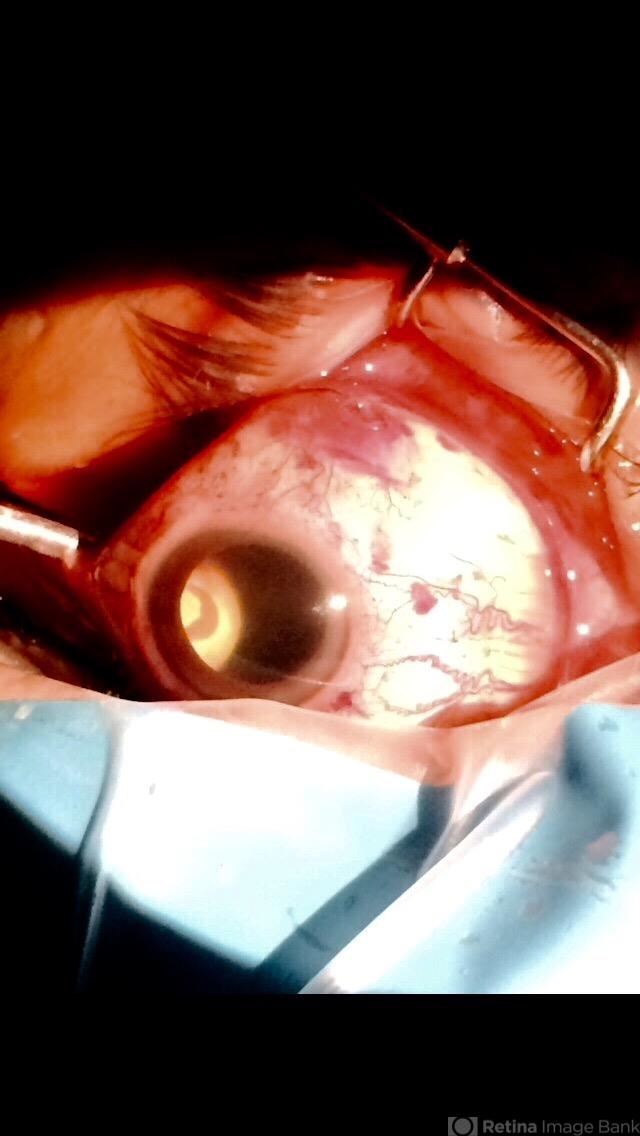

- acute retinal detachment, cryotherapy, scleral buckle

- 35mm external camera

- Photograph of the right eye of a 58-year-old male patient with a retinal detachment due to a peripheral horseshoe tear, showing the moment when cryotherapy is applied during the scleral bluckling procedure.